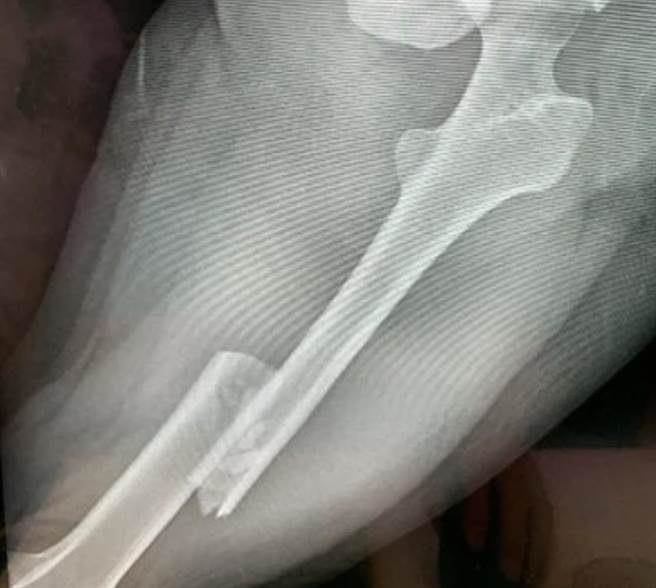

被害人遭前男友开车衝撞、辗压,造成她的骨盆、左大腿骨折。(本报资料照片)

被害人说,当天她开后座车门拿行李时突然遭撞,当场倒卧在车旁地上无法起身,「 上半身还有感觉,但下半身就没办法动,对方竟倒车再加速往我身上辗压」,造成她的骨盆、左大腿骨折,长官见状赶快将她移到路边,以免再度被撞。